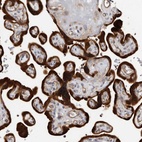

Immunohistochemical staining of human placenta shows strong cytoplasmic and nuclear positivity in trophoblastic cells.